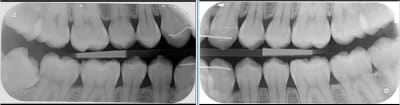

c'est sur que le capteur c'est beaucoup plus rapide, mais moi je préfère les film a l'usage.

apres je fais pas trop de bilan... j'attends plutot les signes d'appel ;)

sinon avec le film chez les jeunes tu peux faire ca, pour le depistage des caries:

Quel est ton générateur pour avoir une émission aussi large ? Et j'apprécie toujours autant les porte-plaques que tu m'as conseillé.